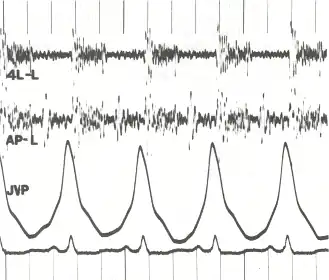

Phonocardiogram and jugular venous pulse tracing from a middle-aged man with pulmonary hypertension (pulmonary artery pressure 70 mm Hg) caused by cardiomyopathy. The jugular venous pulse tracing demonstrates a prominent a wave without a c or v wave being observed. The phonocardiograms (fourth left interspace and cardiac apex) show a murmur of tricuspid insufficiency and ventricular and atrial gallops.[1] | |